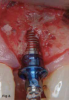

Osseodensification burs create real-time haptic feedback, which informs the surgeon if more or less force is needed and allows immediate adjustments to be made to the advancing force, depending on the given bone density. These burs rotate in a counterclockwise direction and do not "cut" as expected with standard burs (Figure 5). They, therefore, densify bone by rotating in the noncutting direction (counterclockwise at 800 to 1,200 rotations per minute). Copious amounts of irrigation fluid should be used during the procedure to provide adequate lubrication between the bur and bone surfaces to minimize overheating. When used correctly, at the proper high speed and in a reversed, noncutting direction with steady external irrigation, a strong, dense layer of bone tissue can be formed along the walls and base of the osteotomy.

Fig 5. The osseodensification bur technology is based on a novel biomechanical bone preparation technique. Unlike traditional dental drilling techniques, osseodensification does not excavate bone tissue. Rather, bone tissue is simultaneously compacted and autografted in outwardly expanding directions from the osteotomy. Osseodensification burs feature four or more lands that precisely guide the bur through bone via a specifically engineered design. The burs produce a controlled bone plastic deformation, which allows the expansion of a cylindrical osteotomy without excavating any bone tissue.

Figure 5